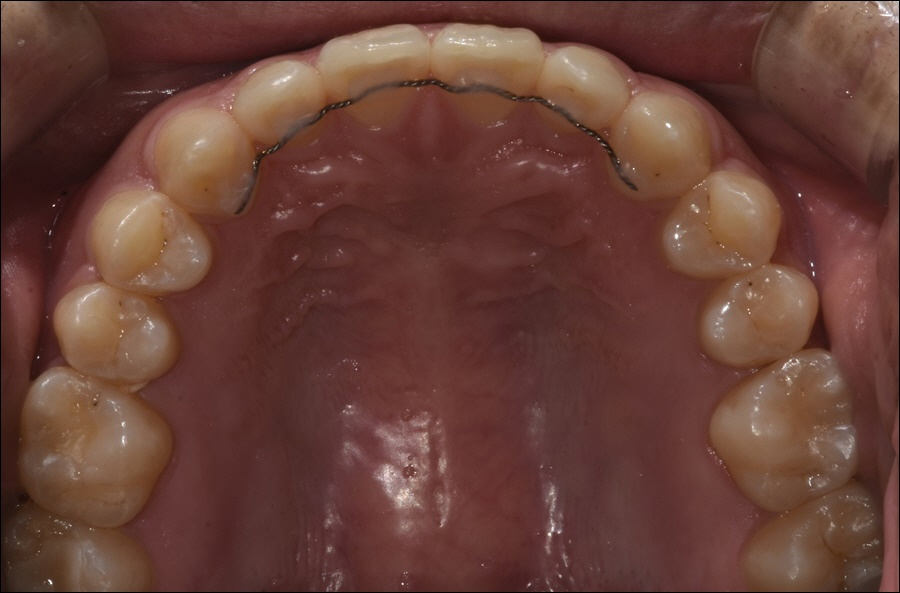

또한, 의학 기술의 끊임 없는 발전으로

다양한 교정 장치가 등장하고 있었어요.

특히, 환자분들의 니즈에 맞춘 투명한

소재의 장치들이 인기를 끌고 있었으며,

투명 "인비절라인" 장치의 경우,

전 세계적으로 사랑을 받고 있었습니다.

이는 미국 FDA 승인을 받아 더욱 신뢰할 수

있는 안전한 교정 장치라 할 수 있었어요.

이렇듯 신논현치과에서 진행하고 있는

인비절라인은 투명한 특수 재질의

플라스틱으로 제작되고 있기 때문에

치아 교정을 진행하고 있는 기간에도

심미적으로도 만족스럽게 치아를

가지런하게 이동시킬 수 있었습니다.

더불어 탈착이 가능한 장치이기 때문에

위생 관리에도 용이하였으며, 음식물을

섭취하거나 칫솔질을 할 때, 뺄 수 있었어요.

또한 1:1 맞춤으로 제작되기 때문에

이물감이 적다는 것이 장점으로 꼽히고

있었으며, 발음도 정확하게 구사했어요.